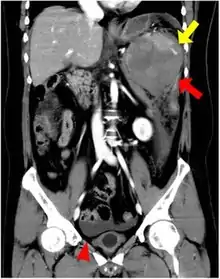

Accessory spleens may undergo hypertrophy after splenectomy[15] Very rarely, it may cause bleeding (pictured).[16]

16. Note: The case is possibly splenosis rather than an accessory spleen:

Maki, Takehiro; Omi, Makoto; Ishii, Daisuke; Kaneko, Hiroyuki; Misu, Kenjiro; Inomata, Hitoshi; Tateno, Masatoshi; Nihei, Kazuyoshi (2015). "Spontaneous hemorrhage from splenic tissue 13 years after total splenectomy: report of a case". Surgical Case Reports. 1 (1): 91. doi:10.1186/s40792-015-0099-0. ISSN 2198-7793. PMC 4593983. PMID 26943415.